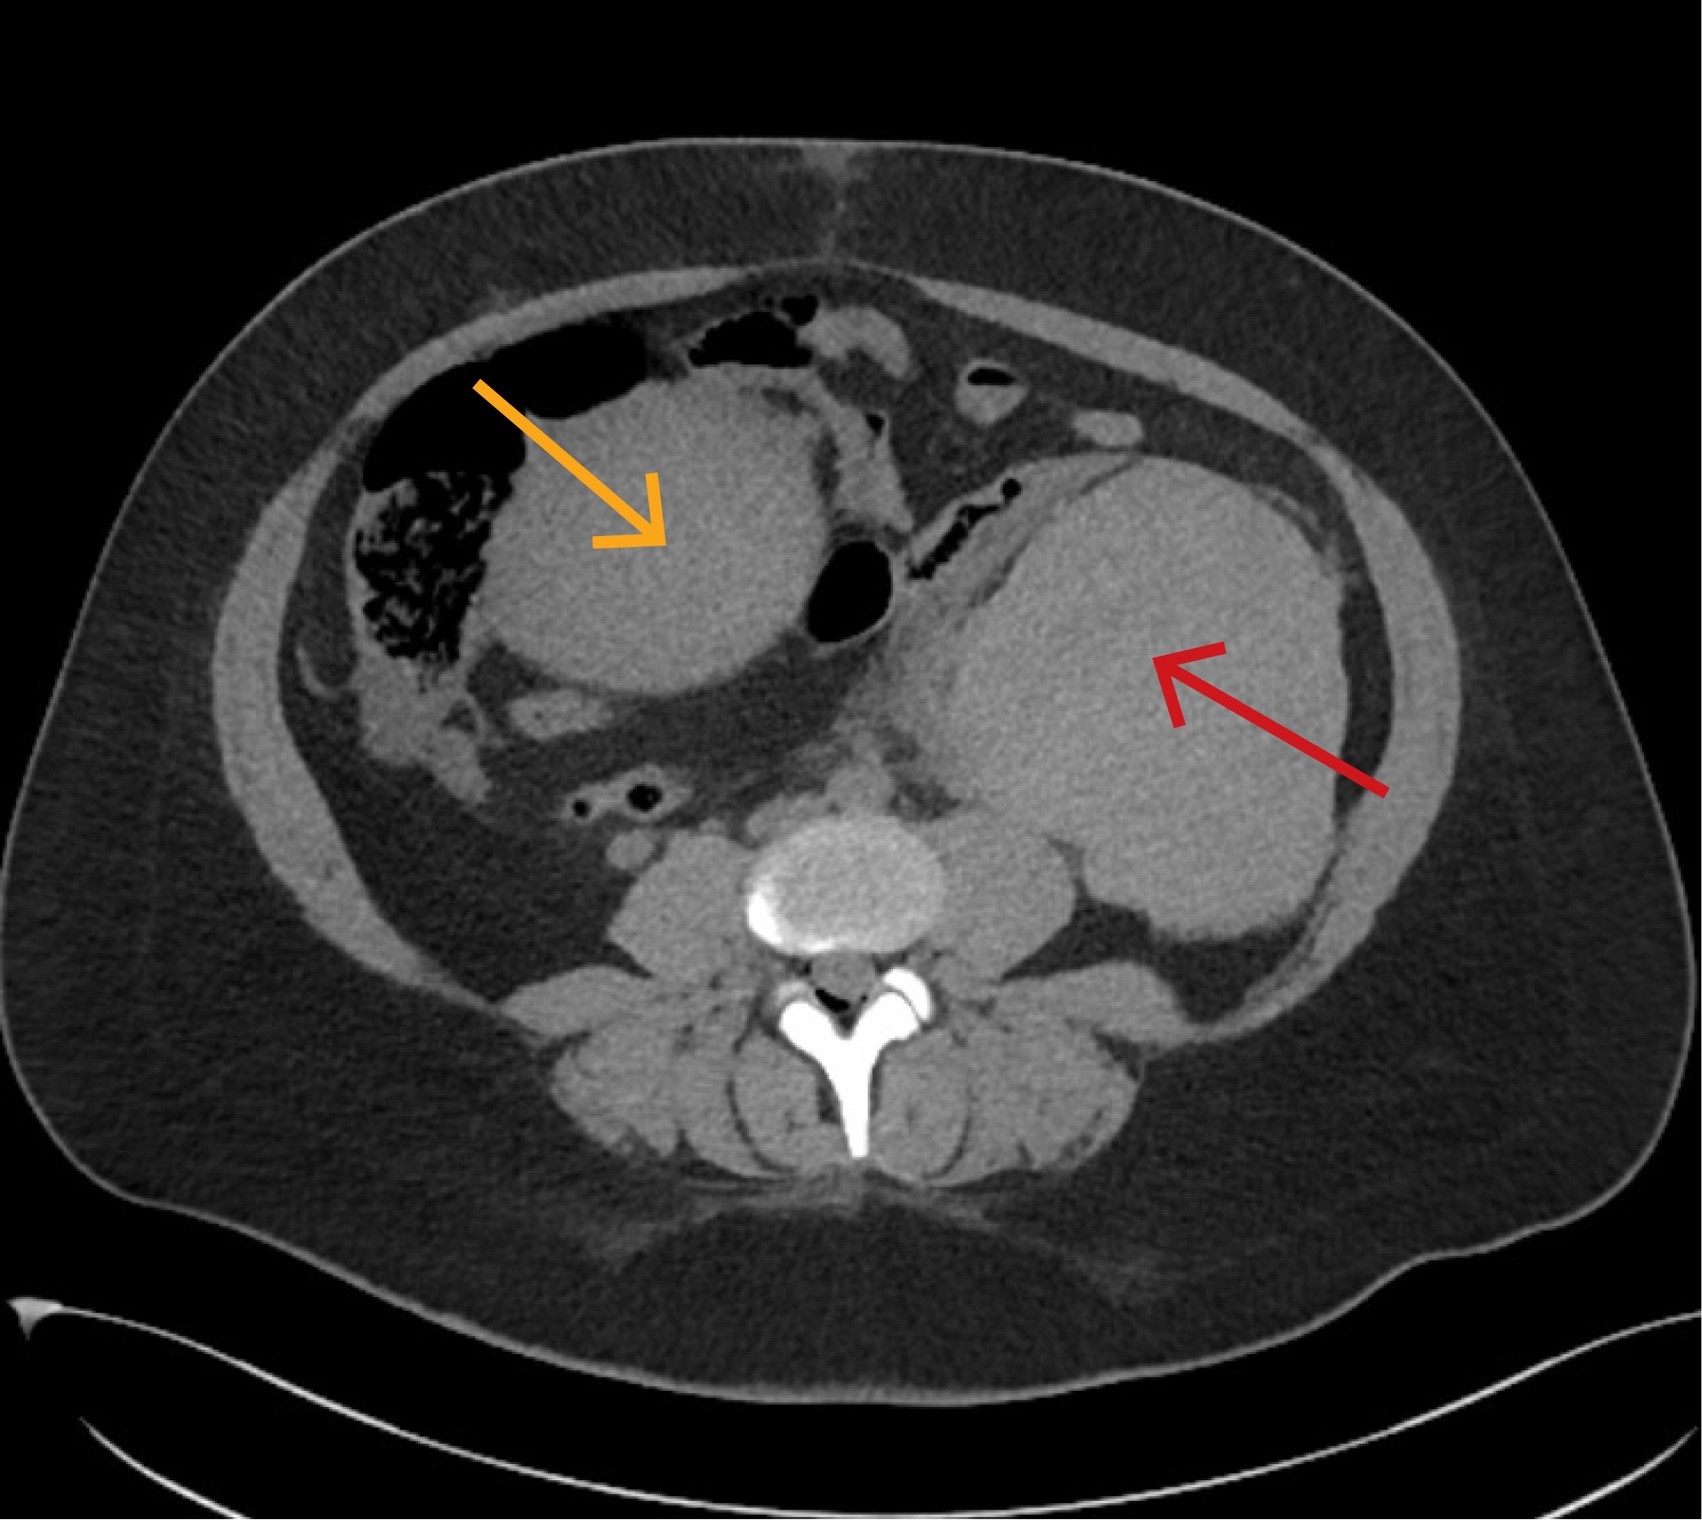

3,5 timer postpartum ble CT abdomen/bekken uten kontrast tatt, og radiolog beskrev et stort intraperitonealt hematom på venstre side av uterus (figur 1). Siden pasienten var sirkulatorisk ustabil, kjørte man rett på operasjon for innleggelse av sentralt venekateter, blodtransfusjon og kirurgisk intervensjon uten ytterligere bildediagnostikk.

Åtte dager postpartum begynte pasienten plutselig å blø rikelig vaginalt. Ambulansepersonell mistenkte alvorlig blødning med estimert mengde på 2–3 L, og bestilte kriseblod. Blodtrykk lå mellom 56/34 og 101/66 mmHg, og puls var 135 per minutt. Hun ble oppfattet som hemodynamisk ustabil, og grunnet værforhold ble hun fløyet til et universitetssykehus med luftambulansehelikopter istedenfor til fødesykehuset. Under transporten var pasienten våken, og blodtrykket ble målt fire ganger til rundt 110/70 mmHg, pulsen gradvis fallende til 126 per minutt. Det ble gitt en pose RhD-positivt blod, en pakke LyoPlas (frysetørret plasma), og traneksamsyre 2 g intravenøst. Hun ble møtt av kirurgisk mottaksteam på universitetssykehuset. Det var normalt blodtrykk, puls 108 per minutt og ingen pågående vaginalblødning. Ultralyd abdomen viste ingen fri væske. CT avdekket et stort retroperitonealt hematom med mistenkt aktiv blødning og et mindre hematom i cervix/vagina (figur 3). Bildene fra fødselsinnleggelsen ble gransket på nytt, og man så for første gang at hematomet som var beskrevet som intraperitonealt ved fødesykehuset, også da hovedsakelig lå retroperitonealt.

Vår pasient hadde alvorlige symptomer som kunne stamme fra flere organsystemer. En bred tilnærming var derfor viktig for å finne riktig diagnose. En intensivseng er på sitt beste en perfekt plass for et slikt kollokvium. Det viste seg at pasienten hadde blødningssjokk forårsaket av uterusruptur med både uvanlig presentasjon og lokalisasjon av påfølgende hematom. Sammen med en initial tolkning av hematomet som intraperitonealt bidro dette til å forsinke diagnosen. CT ble først protokollert og utført uten intravenøs kontrast, noe som riktignok påviste blødning, men som vanskeliggjorde vurdering av lokalisasjon og omfang av dette. Påfølgende serier med intravenøs kontrast ble ikke gjort da pasienten ble oppfattet som sirkulatorisk ustabil og tatt rett til operasjon. Som hovedregel bør pasienter som man mistenker har pågående blødning eller sirkulatorisk sjokk, få utført flerfaset CT med intravenøs kontrast, med eller uten «tomserie».